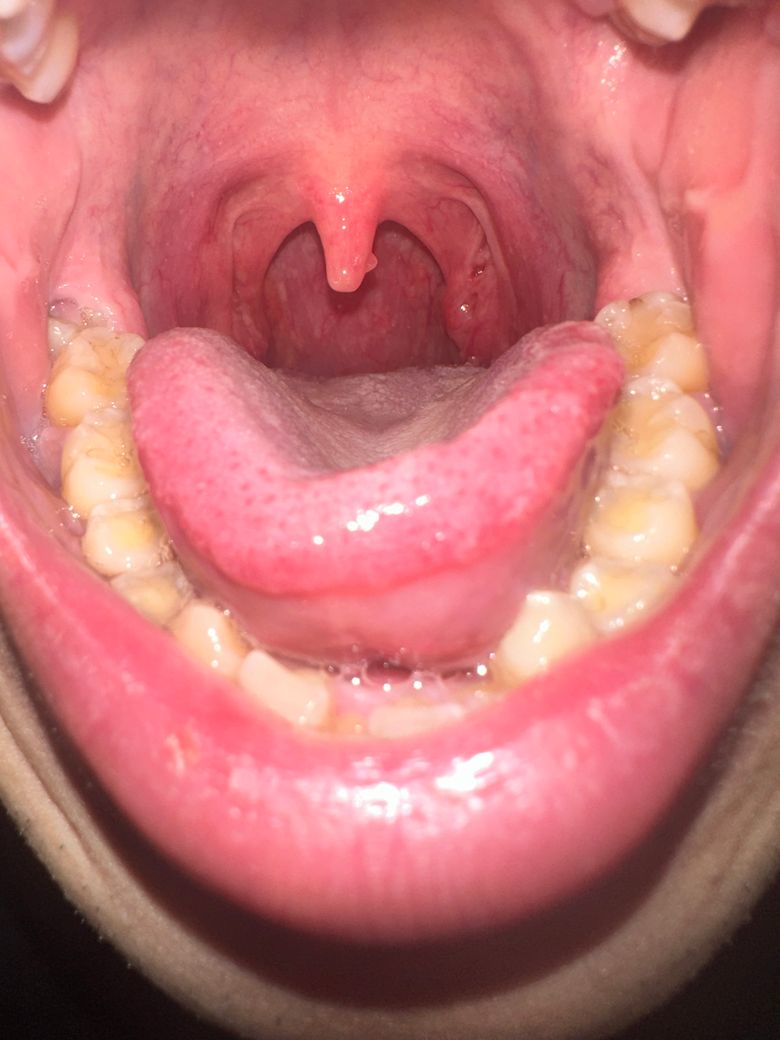

목젖 뒷면 혹이 있어서 확인 부탁드립니다.

올해 1월부터 목젖 뒷면에 혹이 관찰되었습니다.

아래 사진은 지금 사진이고요

점점 위치랑 보이는 면적이 변하는것 같아 문의드립니다.

근처 이비인후과에선 지켜보자고 했는데요.

• 2번 째 사진

특이소견은 아닌것으로 보여집니다.

굳이 지금 치료하지않고 지켜보셔도 될것같습니다.

신경쓰지말고 지내보세요.

• 안녕하세요. 최성훈 의사입니다.

이비인후과 전문의 진찰 후 경과 관찰로 설명을 들었다면 당장 큰 문제는 아니겠으나 추후 변화 확인을 위해 재진료를 받으시기 바랍니다.